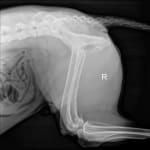

- Radiographs

- Radiographs are normal

- MRI normal–ruled out a tumor, fracture, or infarct

- Diagnosis of DM through elimination–using PE findings and supportive genetic test results